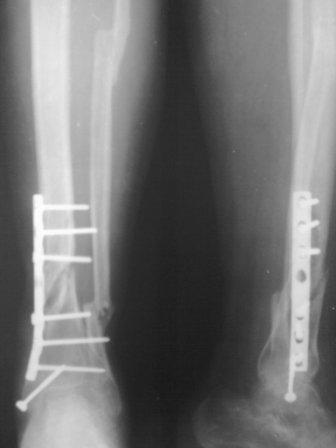

Состояние раны ч-з две недели, покрыт корочкой, подним идет хорошая грануляция, повязка только димексид с фурациллином, пока нагноения нет, выделения из раны нет, 5 дней уже антибиотиков не принимает. Фото и рентген прилагается.

Как Джолдас предлагал спицы удалены, в дистальном кольце три спицы, рекомедована дозированная нагрузка, и больной выпысан. приедит ч-з две нед.